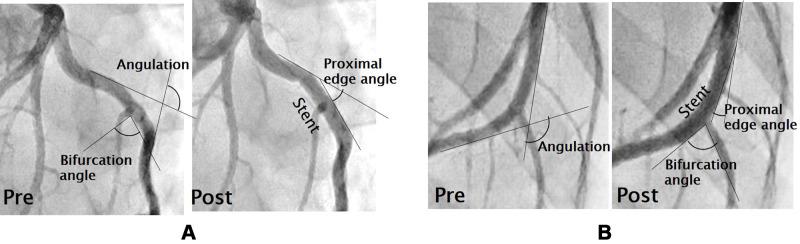

Implantation of both stents significantly increased site angulation (Multi-link 8: 148° ± 8° to 172° ± 2°, p < 0.05, paired -test; Kaname: 152° ± 5° to 164° ± 4°, p < 0.05, paired -test), but the change tended to be greater after Multi-link 8 stent implantation (24° ± 15° vs 11° ± 7°, p = 0.1, -test), suggesting greater straightening of the bifurcation. The Multi-link 8 stent induced greater neointimal thickness than the Kaname stent (0.53 ± 0.3 mm vs 0.26 ± 0.1 mm, p < 0.05, -test). The distribution of neointimal hyperplasia following stent implantation as revealed by longitudinal histopathology matched the distribution of WSS simulated using computational fluid dynamics (CFD). The endothelium at low WSS areas exhibited aberrant cell morphology and leukocyte adhesion. A CFD model of a curved bifurcation suggested that the region of low WSS is expanded by artery straightening.